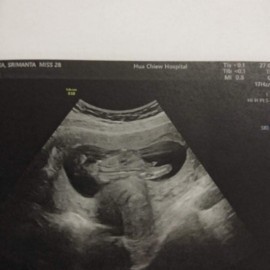

ในภาพเป็นภาพด้านหลังกับด้านข้าง มองไม่ออกค่ะ ขาบังอยู่ หมอไม่ได้บอกหรอคะ?

หมอจะบอกแม่เองคะ